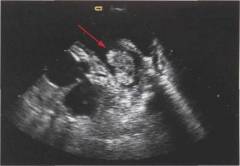

Эхокардиография

Эхокардиография (УЗИ сердца) — важный метод диагностики, который точно подтверждает диагноз и предоставляет полезную информацию. Метод основан на использовании ультразвуковых волн, направляемых к сердцу через грудную стенку. Отраженные волны возвращаются к датчику, формируя изображение на экране. Современные аппараты могут считывать данные с двух датчиков одновременно, создавая объемное изображение. Во время ЭхоКГ врач получает динамическую картину работы сердца, что важно для его оценки.

Эхокардиография позволяет выявить признаки аневризмы сердца:

- локальное выпячивание стенки сердца;

- истончение стенки аневризмы по сравнению с миокардом;

- дискинезия миокарда (стенка аневризмы не участвует в сокращениях или отстает в ритме);

- разделение аневризм на систолические (меньшие, видимые в систолу) и диастолические (заметные в любой фазе);

- определение ширины перешейка (важно для выявления ложных аневризм);

- обнаружение тромбов в полости аневризмы или левого желудочка;

- выявление жидкости в полости перикарда;

- оценка функционирования клапанов;

- измерение диаметра и объема камер сердца (важно для определения причин сердечной недостаточности);

- анализ направления и скорости кровотока в камерах сердца (важно для прогнозирования тромбообразования).

Таким образом, ЭхоКГ предоставляет полную информацию о заболевании. На основе исследования аневризма классифицируется по форме, размерам и другим параметрам, что позволяет сформировать прогноз и разработать стратегию лечения.